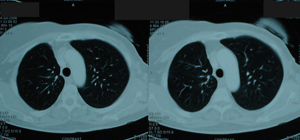

Εικόνα 3

Αξονική τομογραφία θώρακος που δείχνει μάζα εκ μαλακών μορίων στο πρόσθιο τμήμα του δεξιού άνω λοβού. Η μάζα έχει ομοιογενή σύσταση με ομαλά όρια.